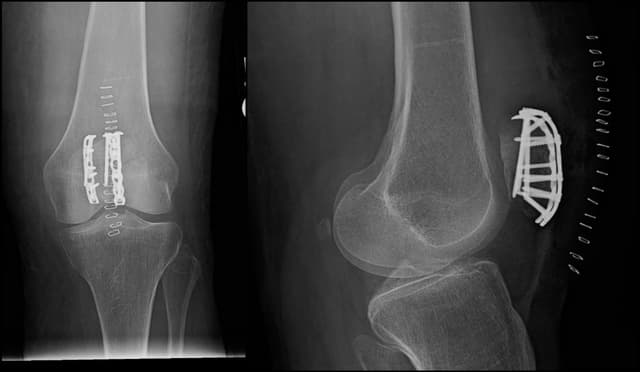

Patella ORIF

Pre-op

Post-op